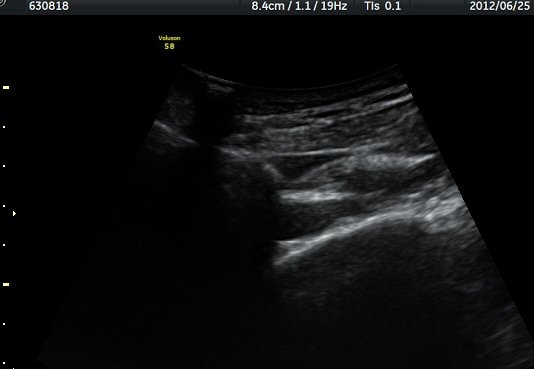

¾î±ú °üÀý µÚÂÊ ÈĹæ°üÀý¼ø Ⱦ´Ü¸é°Ë»ç¿¡¼­ °üÀý¼ø ³»Ãø, °¡½Ãµ¹±â°üÀý¼ø°í¶û(spinoglenoid

notch)¿¡¼­ Àú¿¡ÄÚ ³¶Á¾ÀÌ °üÂûµÈ´Ù(±×¸² 1). ŽÃËÀÚ¸¦ À§-¾Æ·¡ ¹æÇâÀ¸·Î º¯°æÇÏ¿© °üÂûÇÒ ¶§µµ

¿ª½Ã °ß°©°ñ °¡½Ãµ¹±â(spine) ¾Æ·¡¿¡¼­ Àú¿¡ÄÚ ³¶Á¾ÀÌ °üÂûµÈ´Ù(±×¸² 2). º¼·ÏŽÃËÀÚ·Î ¹Ù²Ù¾î °ü

ÂûÇÏ´Ï  °¡½Ãµ¹±â°üÀý¼ø°í¶û¿¡¼­ Àú¿¡ÄÚ ³¶Á¾ÀÌ ´õ¿í ¶Ñ·ÈÈ÷ °üÂûµÈ´Ù(±×¸² 3, 4).

ÁÖ»ç¹Ù´Ã ÈíÀÎ(µ¿¿µ»ó Âü°í) 4ÀÏ ÈÄ °üÂûÇÑ ¼Ò°ß¿¡¼­´Â ³¶Á¾ÀÇ Å©±â °¨¼Ò°¡ ¶Ñ·ÈÇÏÁö ¾Ê´Ù(±×¸² 5, 6).